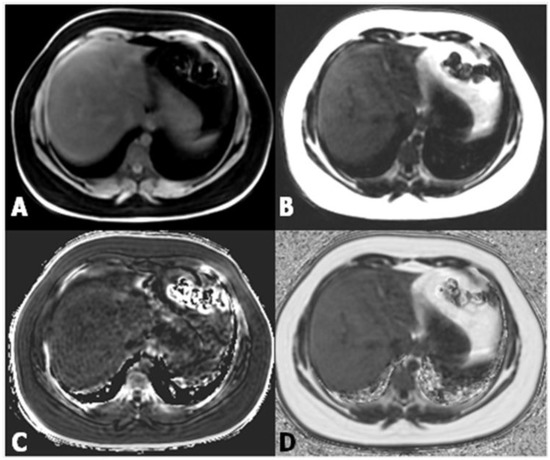

Controlled attenuation parameter (CAP) has been proposed as a non-invasive method for the determination and measurement of hepatic steatosis. The mechanism of CAP is the reduction in amplitude of ultrasound that can be estimated as it is amplified through the liver tissue. This procedure uses the same radio-frequency data used for estimation of liver stiffness with Fibroscan (Echosens, Paris, France), an ultrasound-based vibration-controlled transient elastography device [12], comparing shear stiffness to that of a normal liver, which is between 6.5 and 7 kPa (Figure 2).

Figure 2.

(A) Measurement of liver stiffness shows an estimated Young’s modulus of 2.0 kPa, below the cut-off for the diagnosis of stage F1 fibrosis; (B) Measurement of liver stiffness shows an estimated Young’s modulus of 11.5 kPa which reveals the presence of fibrosis.